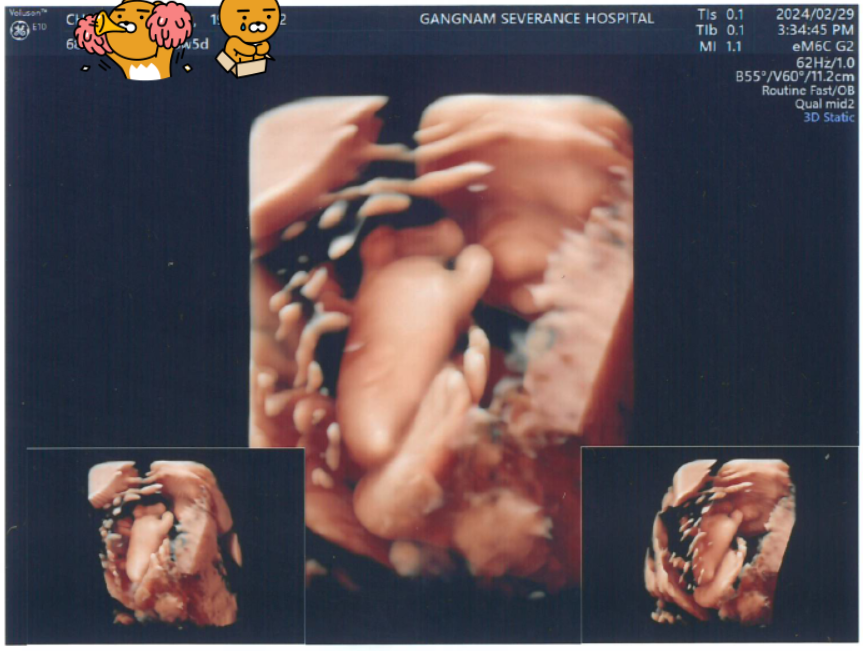

오늘은 비급여로 진행되는 입체초음파 날.

(OMG, 20만원이었어!!!)

아직까지도 몇 장은 왜 주는지 모르겠다.

이건 내가 T여서 그런건가?

F인 엄마들은 정체모를 사진 한장한장 모두 소중하겠지;;?

흑백 초음파보다는 역시 입체초음파 사진이 훨씬 좋다.